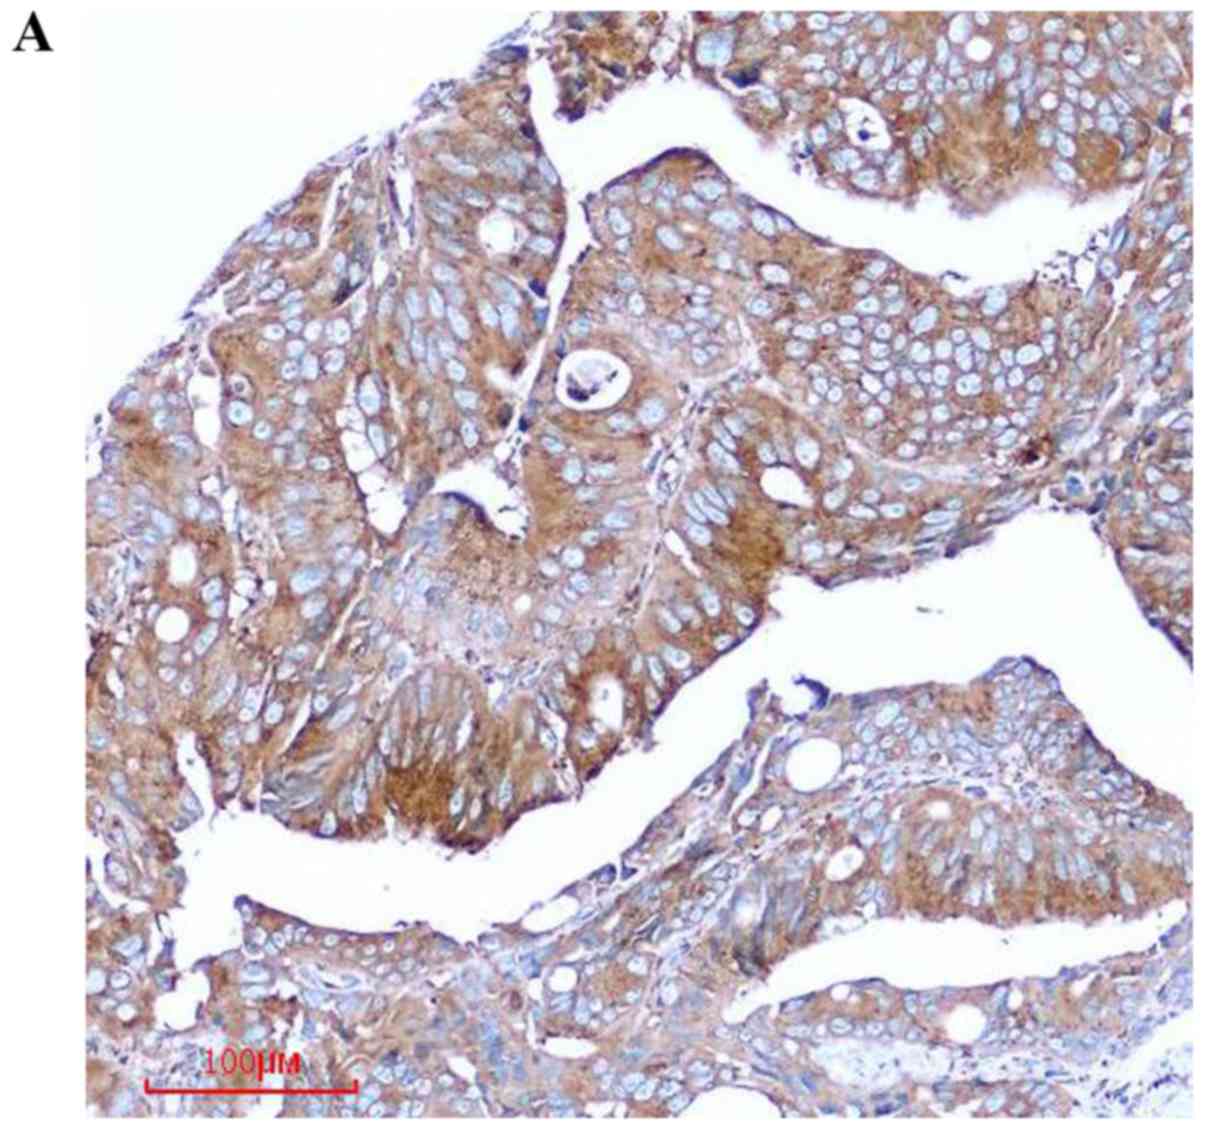

To investigate the relationship between COPB2 expression and human colon cancer, IHC was used to detect COPB2 expression in 35 colon cancer tissues and adjacent noncancerous tissues. We found that COPB2 staining was markedly stronger in the colon cancer tissues than in the paracancerous tissues (Fig. 1A). Notably, the COPB2 protein density was determined to be 4.60±1.418 in the human colon tissues and 1.17±1.098 in the corresponding adjacent tissues (P<0.001; Table I and Fig. 1B). These results indicated that COPB2 may be involved in the pathogenesis of human colon cancer.

Figure 1.

Immunohistochemical analysis of COPB2 expression in colon cancer specimens. (A) High-level expression of COPB2 in colon cancer tissues. (B) Low-level expression of COPB2 in paired adjacent noncancerous tissues. COPB2, coatomer protein complex subunit β2.